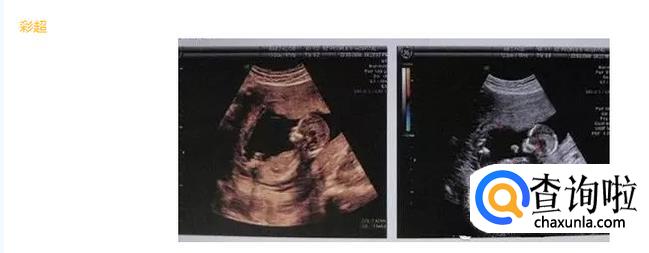

彩超并不是你们所想的字面意义上理解的“彩色的B超”,只是在普通B超的基础上出现了彩色多普勒超声波探测诊断技术。彩超其实还是黑白的,被称为彩超,是因为会用彩色标注心脏、血流等指标。彩超的分辨率会比一般B超高一些,所以在需要做比较细致的检查的时候,更多的医生愿意通过彩超来检查。彩超可以检测出宝宝内脏的情况以及有脐带绕颈的情况。